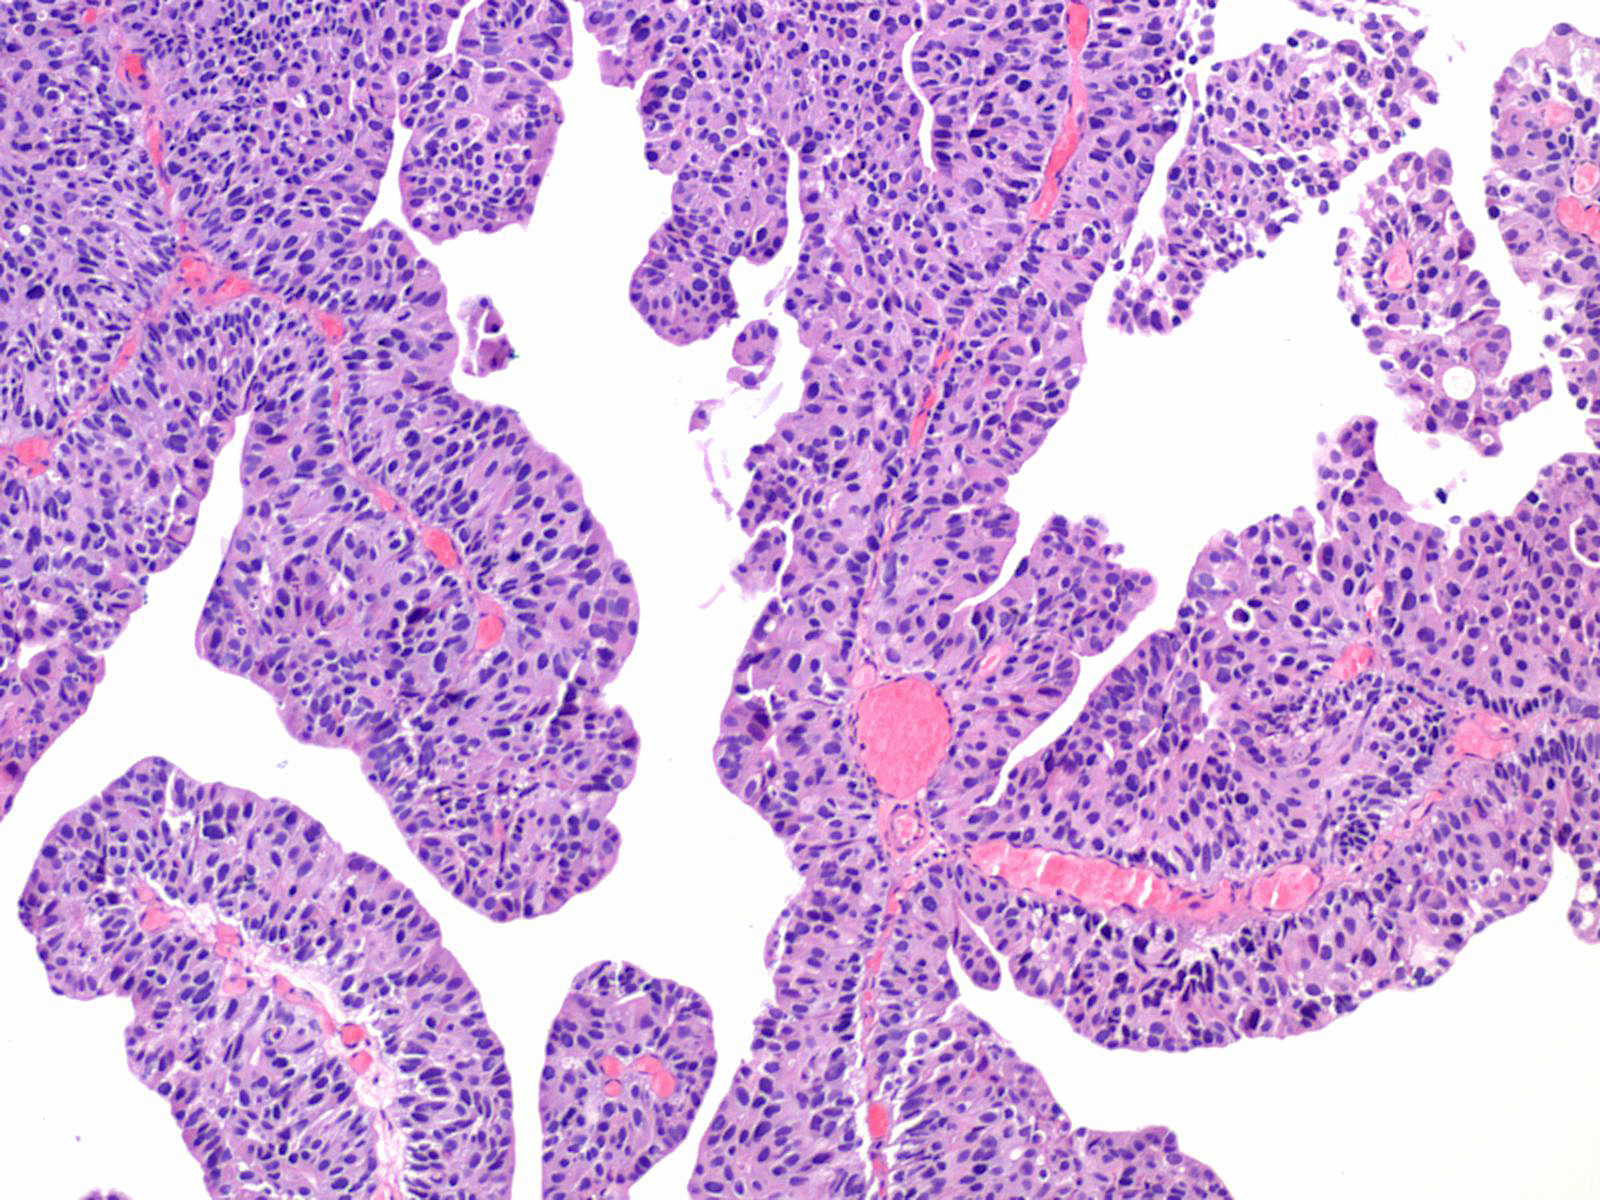

Consensus grade: High-grade papillary urothelial carcinoma (HG-PUC)

Lesion shows marked variation in nuclear size, shape and chromatin. Architecturally, cells appear irregularly clustered and the epithelium is disorganized. Mitotic figures are frequently seen at all levels.